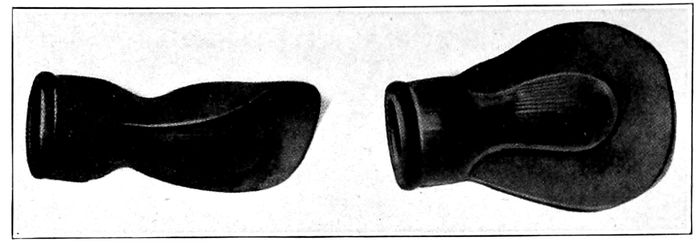

| 108. |

Examples of imperfect nipples |

245 |

| |

| 109. |

A standard nipple shield |

246 |

| |

| 110. |

A standard breast pump |